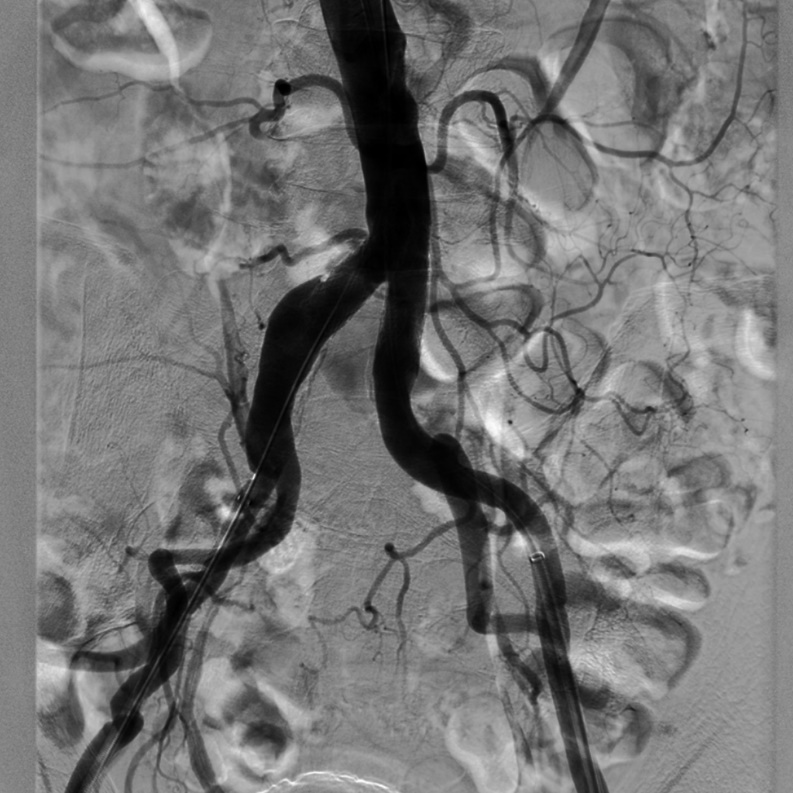

(2)泥鳅导丝配合PIGTAIL导管进入腹主动脉,行主髂动脉造影显示:右侧髂总动脉重度狭窄,走行迂曲,后伴狭窄后扩张;双侧髂内、髂外动脉显影正常。

导丝怎么扩【问术ASK】佟铸教授:双侧髂总动脉“对吻”球扩覆膜支架植入术_https://www.jmylbn.com_新闻资讯_第4张

(3)建立右侧股总动脉逆行入路后,泥鳅导丝配合VER导管通过髂总动脉病变后,双侧入路交换为260cm加硬泥鳅导丝,随即透视监视下导入 8F*45cm长鞘至双侧髂外动脉近端;延右侧导丝进入INVETEC 5*40mm球囊行右侧髂总动脉狭窄病变预扩张。